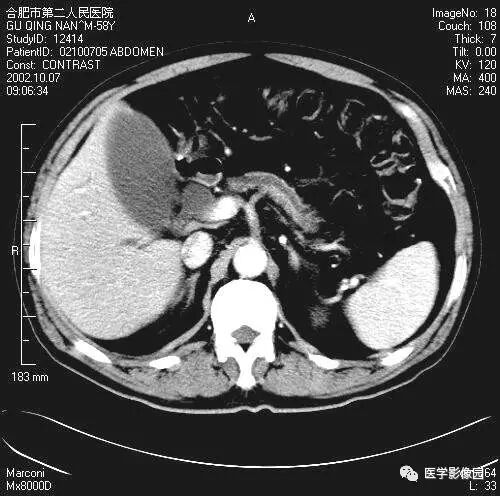

图6-4-19胰腺癌

A.B增强扫描见胰体部肿大,

继发性潴留囊肿形成(↑),

肝右叶转移灶(长↑)